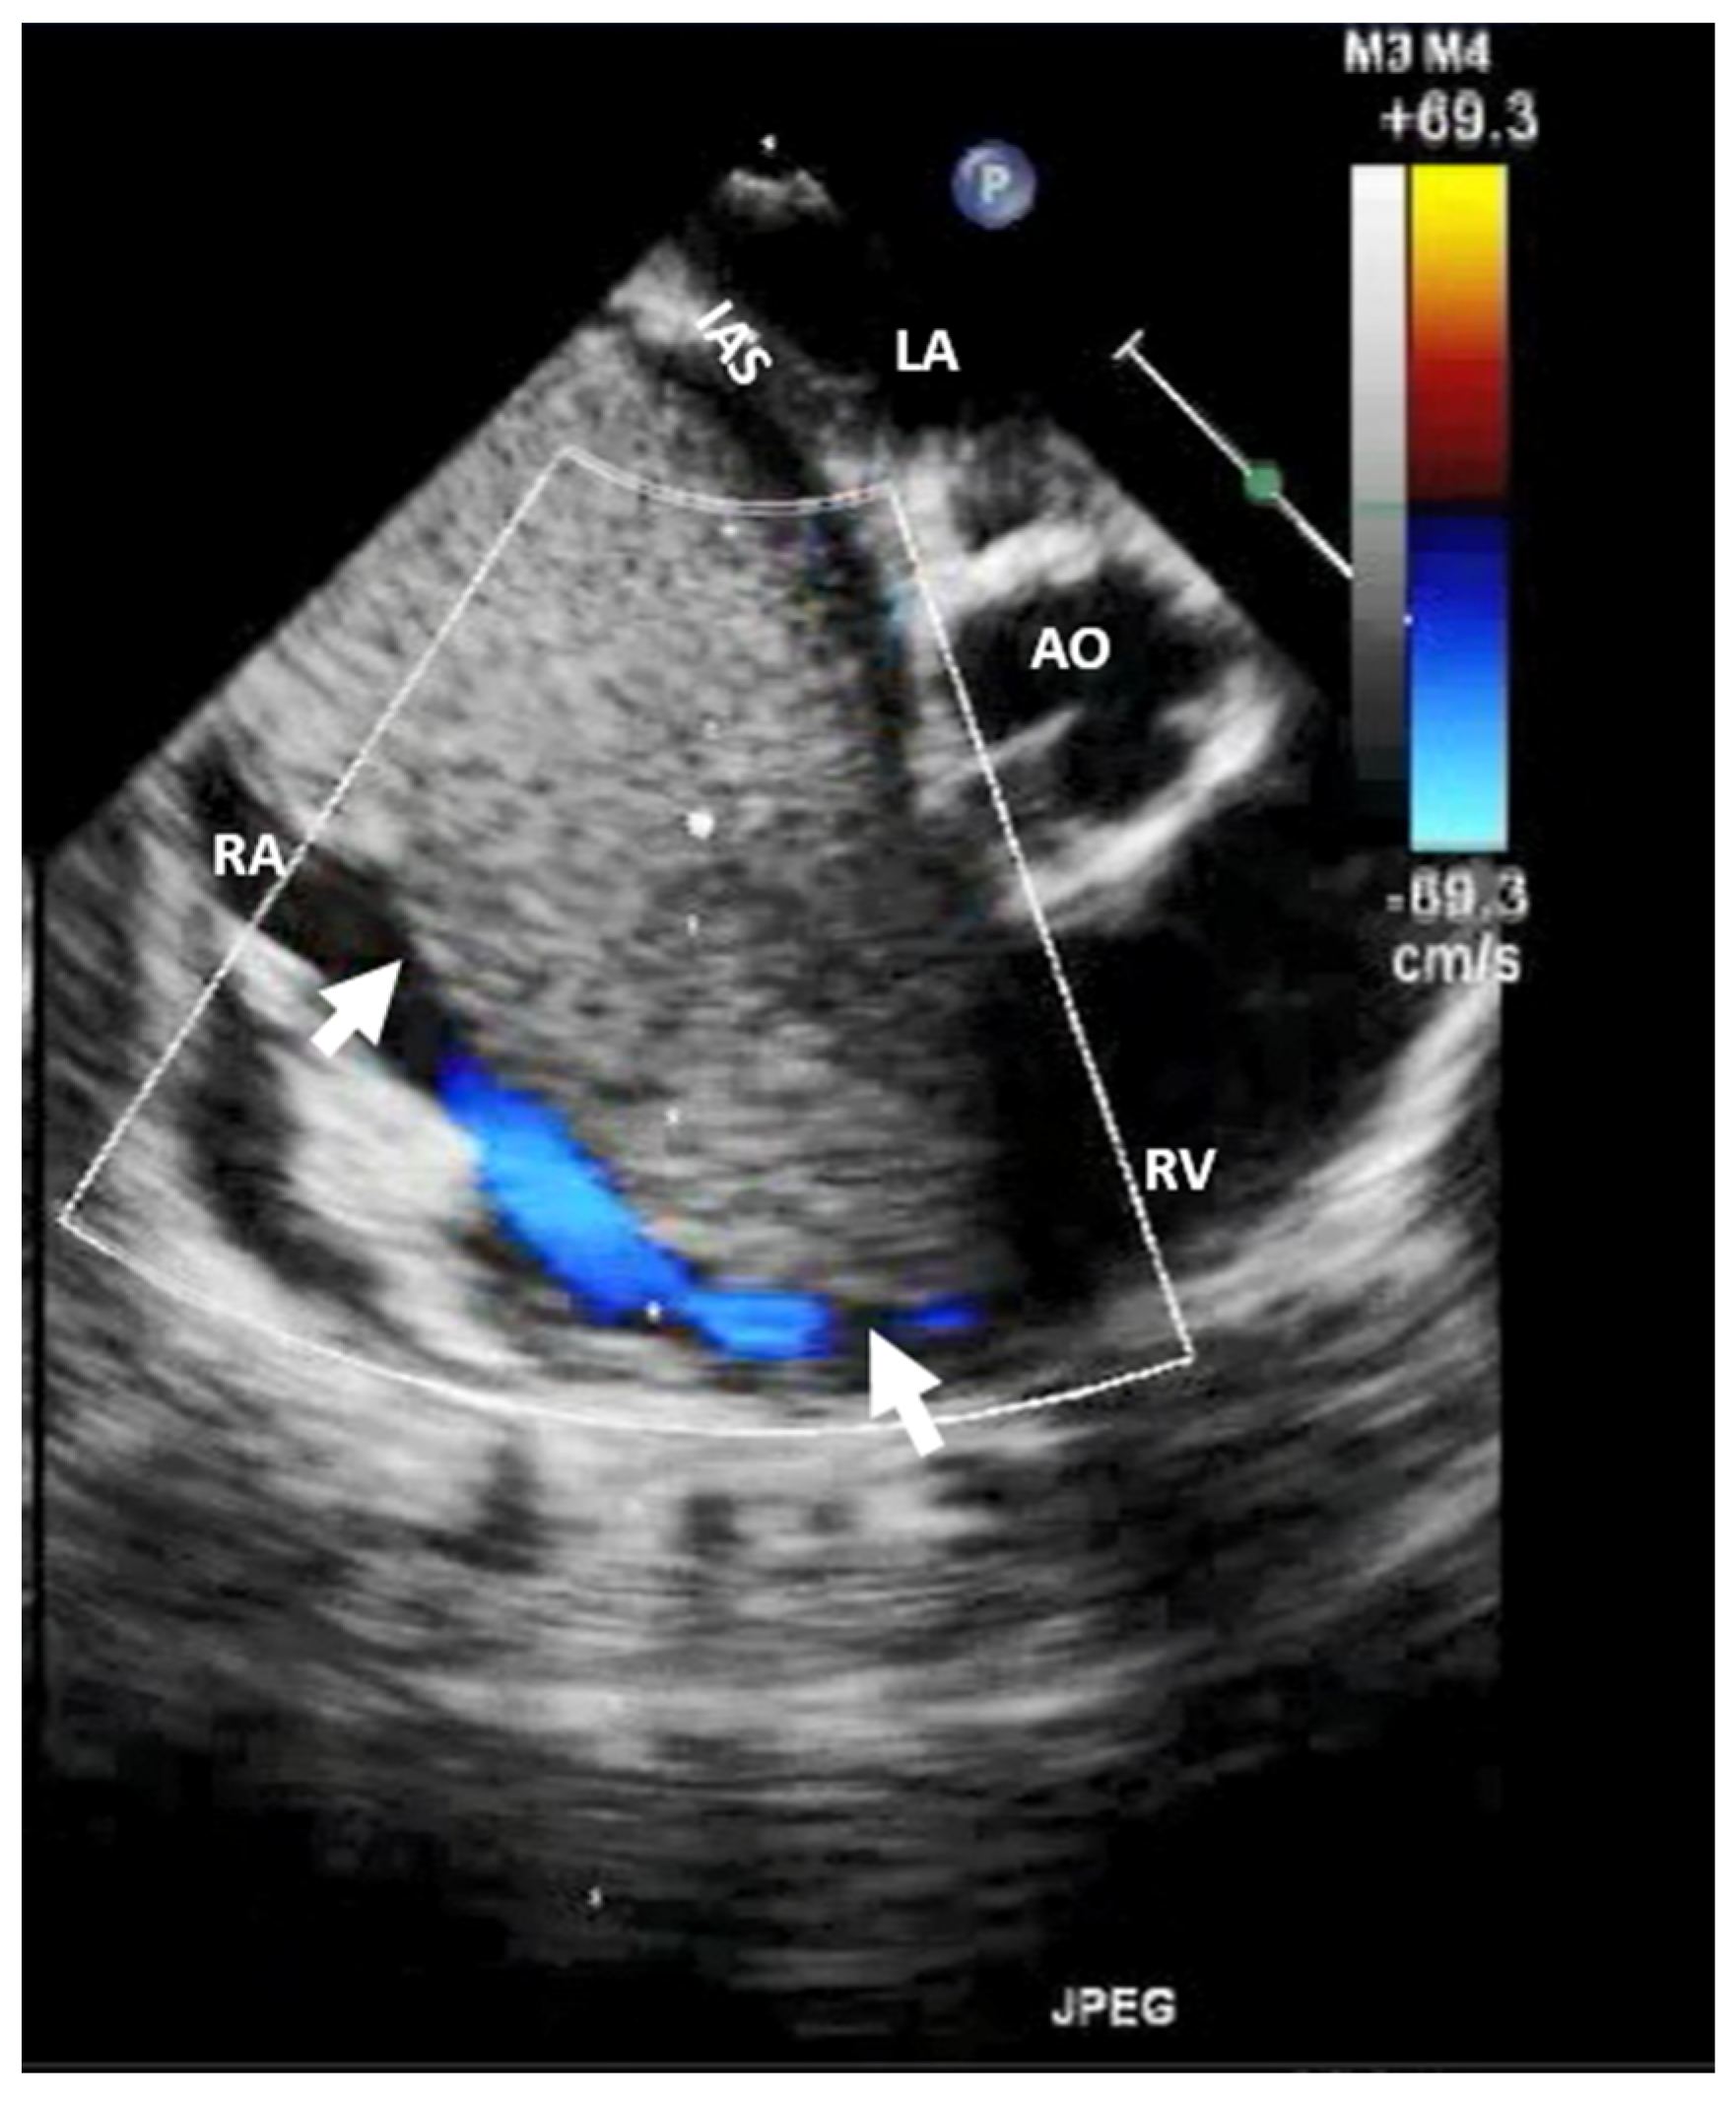

| HEMANGIOMA: It is an incidental finding; if symptomatic, the patient can present with chest pain, arrhythmias, heart failure, dyspnea on exertion, syncope, stroke, pericardial effusion, cardiac tamponade, and even sudden death. | It appears as a well-defined structure, endocardial or intramural, with oscillations during the cardiac cycle, good vascularization (it presents blood flow signals on color Doppler flow imaging), and obvious enhancement. | It is a well-defined structure with low or equal density, associated with heterogeneous intense enhancement and “vascular blush” on coronary angiography. | It appears on T1WI as heterogeneous isointense or hypointense, and on T2WI as hyperintense with heterogeneous enhancement. | It is usually not necessary, except in cases of suspected malignancy. |